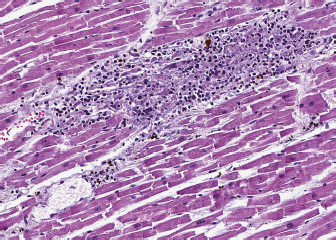

A 4-year-old spayed female mixed-breed dog was referred with a 1-month history of regurgitation and progressive generalized weakness. At the time of presentation, the general physical examination was unremarkable. The neurologic examination revealed exercise intolerance, with the development of weakness beginning in the hindlimbs and progressing into a non-ambulatory flaccid tetraparesis with neck ventroflection, which was alleviated by rest and bilateral symmetrical reduction of patellar, tibialis cranialis, and withdrawal of reflexes. The dog showed mild dysphagia characterized by reduced and difficult swallowing and hypersalivation. The neurologic exam was indicative of a generalized lesion of the low motor neuron system. The neurologic examination was followed by an extended laboratory analysis, including blood counts, serum biochemical profile, coagulation and urinary analysis, and chest radiographs. The haematological abnormalities were a mild increase of WBC (13.1; reference ranges (RR): 5.37–12.39 × 103/mcl) characterized by neutrophilia (11,135; RR: 2,778–8,220 × 103/mcl), lymphocytosis (1,179; 1,009–3,471 × 103/mcl), and monocytosis (655; RR: 155–537 × 103/mcl). Biochemistry revealed significant increase in creatine kinase (CK) (7,934; 39–168 U/l) with a less severe increase of aspartate aminotransferase (AST) (389; 16–39 U/l) and alanine aminotransferase (ALT) (302; 15–79 U/l), moderately elevated C reactive protein (4.54; RR: 0.01–0.41 mg/dl), and hyperferritinemia (776; RR: 38–272 ng/ml). Urinalysis was within normal limits. The thoracic radiographs showed a diffusely dilated esophagus and soft tissue opacity in the cranial mediastinum. The diagnostic suspicion was a form of acquired MG associated with a cranial mediastinal mass although clinically polymyositis could not be completely excluded. A 0.05 mg/kg (0.02 mg/lb) of neostigmine (Prostigmina®) was administered intramuscularly to support our first suspicion. After few minutes, the dog showed a positive result, with increased muscular strength. A computed tomographic (CT) scan examination showed a rounded cranial mediastinal neoformation, characterized by heterogeneous appearance due to the presence of cystic intraparenchymal areas and associated with normal cranial sternal and mediastinal lymph nodes. The CT scan also showed an expansion of the entire esophagus and stomach, mainly due to gas. These findings confirmed a moderate megaesophagus and the presence of a cranial mediastinal mass. A cytological examination and, subsequently, a tru-cut biopsy of the mediastinal mass was performed both with non-diagnostic results. Serum antibodies against ACHRs were highly supportive of MG (5.23 nmol/l; normal in dogs < 0.6 nmol/l). The dog was treated with neostigmine therapy (Prostigmina®) at 0.01 mg/kg (0.004 mg/lb) IM q8h, showing mild improvement of muscular weakness. The cranial mediastinal mass was surgically excised by a median sternotomy. Histology of the formalin-fixed specimen revealed a capsulated, well demarcated, not infiltrative neoplasm, composed of sheets and cords of mildly pleomorphic, spindle to oval cells, multifocally lining variably sized cystic spaces, often filled with eosinophilic secretory material. Neoplastic cells were associated with a moderate number of lymphocytes, forming small multifocal aggregates (Fig. 1). To further characterize the neoplasm, immunohistochemistry was performed using the automated immunostainer Bond RX (Leica Biosystem, Nussloch GmbH; Nusloch, Germany). Antibodies manufacturer, source, clone and dilution are listed in Table 1. The antigen unmasking technique was performed as indicated by the manufacturer. Neoplastic cells were found to express cytokeratin, which exhibited strong cytoplasmatic staining within neoplastic cells lining the cysts, while having a weak to moderate intensity in solid areas. Rare aggregates of desmin and muscle actin expressing cells, interpreted as myoid cells, were also detected.

Fig. 1. Thymoma, dog. Sheets of neoplastic spindle cells are lining multifocal cystic lacunae. Hematoxylin and eosin.